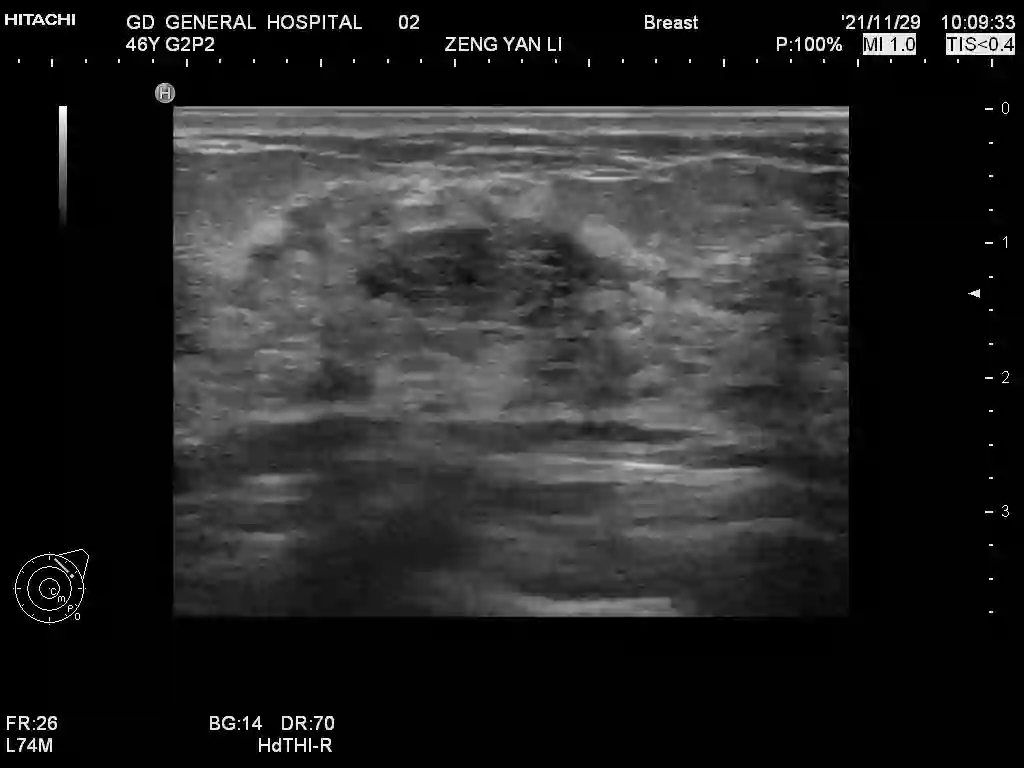

Ultrasonography is an important routine examination for breast cancer diagnosis, due to its non-invasive, radiation-free and low-cost properties. However, it is still not the first-line screening test for breast cancer due to its inherent limitations. It would be a tremendous success if we can precisely diagnose breast cancer by breast ultrasound images (BUS). Many learning-based computer-aided diagnostic methods have been proposed to achieve breast cancer diagnosis/lesion classification. However, most of them require a pre-define ROI and then classify the lesion inside the ROI. Conventional classification backbones, such as VGG16 and ResNet50, can achieve promising classification results with no ROI requirement. But these models lack interpretability, thus restricting their use in clinical practice. In this study, we propose a novel ROI-free model for breast cancer diagnosis in ultrasound images with interpretable feature representations. We leverage the anatomical prior knowledge that malignant and benign tumors have different spatial relationships between different tissue layers, and propose a HoVer-Transformer to formulate this prior knowledge. The proposed HoVer-Trans block extracts the inter- and intra-layer spatial information horizontally and vertically. We conduct and release an open dataset GDPH&GYFYY for breast cancer diagnosis in BUS. The proposed model is evaluated in three datasets by comparing with four CNN-based models and two vision transformer models via a five-fold cross validation. It achieves state-of-the-art classification performance with the best model interpretability.